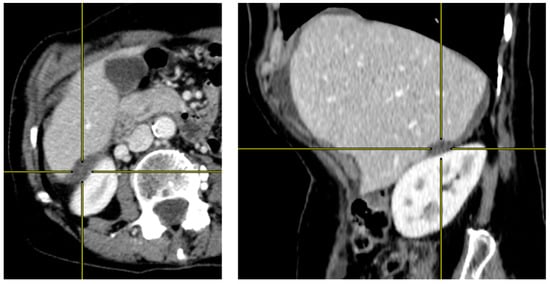

2.2. Preoperative CT-Scan Protocol and Image Analysis

| Liver scalloping 1 | ||||||||

| max depth (mm) | 11.0 [7.0, 17.0] | 21.0 [11.5, 24.0] | 71 (55%) | 0.007 | 11.0 [7.0, 17.0] | 13.5 [10.0, 24.5] | 52 (53%) | 0.2 |

| max depth Hotta (mm) | 14.0 [8.5, 27.0] | 23.0 [18.0, 32.5] | 71 (55%) | 0.038 | 14.0 [7.0, 26.0] | 15.5 [10.8, 25.0] | 52 (53%) | 0.4 |

| max length (mm) | 50.0 [32.5, 66.0] | 60.0 [40.0, 80.0] | 71 (55%) | 0.3 | 48.0 [35.0, 70.0] | 60.0 [43.2, 66.5] | 52 (53%) | 0.3 |

| ratio max depth/length | 0.2 [0.2, 0.4] | 0.4 [0.2, 0.5] | 71 (55%) | 0.10 | 0.2 [0.2, 0.4] | 0.3 [0.2, 0.4] | 52 (53%) | >0.9 |

| Liver + Splenic scalloping 1 | ||||||||

| max depth (mm) | 19.0 [16.0, 34.0] | 32.0 [24.5, 38.0] | 89 (69%) | 0.040 | 27.0 [17.5, 35.0] | 22.0 [16.0, 32.0] | 67 (68%) | 0.6 |

| max length (mm) | 91.0 [70.0, 110.0] | 113.0 [70.0, 128.0] | 89 (69%) | 0.5 | 91.0 [70.0, 107.5] | 88.0 [75.0, 113.0] | 67 (68%) | 0.9 |

| ratio max depth/length | 0.2 [0.2, 0.3] | 0.3 [0.2, 0.4] | 89 (69%) | 0.065 | 0.3 [0.2, 0.3] | 0.2 [0.2, 0.4] | 67 (68%) | 0.4 |

| ROI density (HU) | ||||||||

| ratio ROI scal/aorta ≥ 0.3 | 8 (19%) | 4 (27%) | 71 (55%) | 0.5 | 5 (17%) | 4 (22%) | 52 (53%) | 0.7 |

| ratio ROI scal/liver ≥ 0.6 | 13 (30%) | 8 (53%) | 71 (55%) | 0.13 | 9 (31%) | 8 (44%) | 52 (53%) | 0.4 |